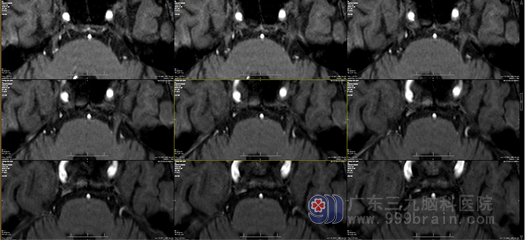

近日我科又来了这样一位愁眉苦脸的患者,来自广东肇庆的陈阿叔,他今年64岁了,被右侧颜面部剧烈疼痛困扰了7年之久了。阿叔7年前无明显诱因出现右侧脸颊发作性疼痛,呈放电样,以右前额为主,每次发作持续时间约一分钟,曾到当地医院就诊,口服药物治后有所缓解,但之后右侧颜面部疼痛发作越来越越频繁,发作严重时可波及右侧下颌、鼻唇沟等位置,甚至连吃饭、刷牙都能引起面部疼痛,只有睡觉才能缓解疼痛,阿叔称最近实在受不了了,有时甚至分不清是头痛还是脸痛,人到老了还要受这种折磨,想想心有不甘,于是在家属的陪同下来到我院就诊。经过外十科医生的接诊,在详细了解了患者病史与病情后,将患者拟“右侧三叉神经痛”收入我科。患者入院头颅MR检查显示:双侧三叉神经经颅内段上方各有一小血管骑跨走行,我科主任欧阳教授判定,患者疼痛应当与其有关。诊断明确,患者有手术指征。